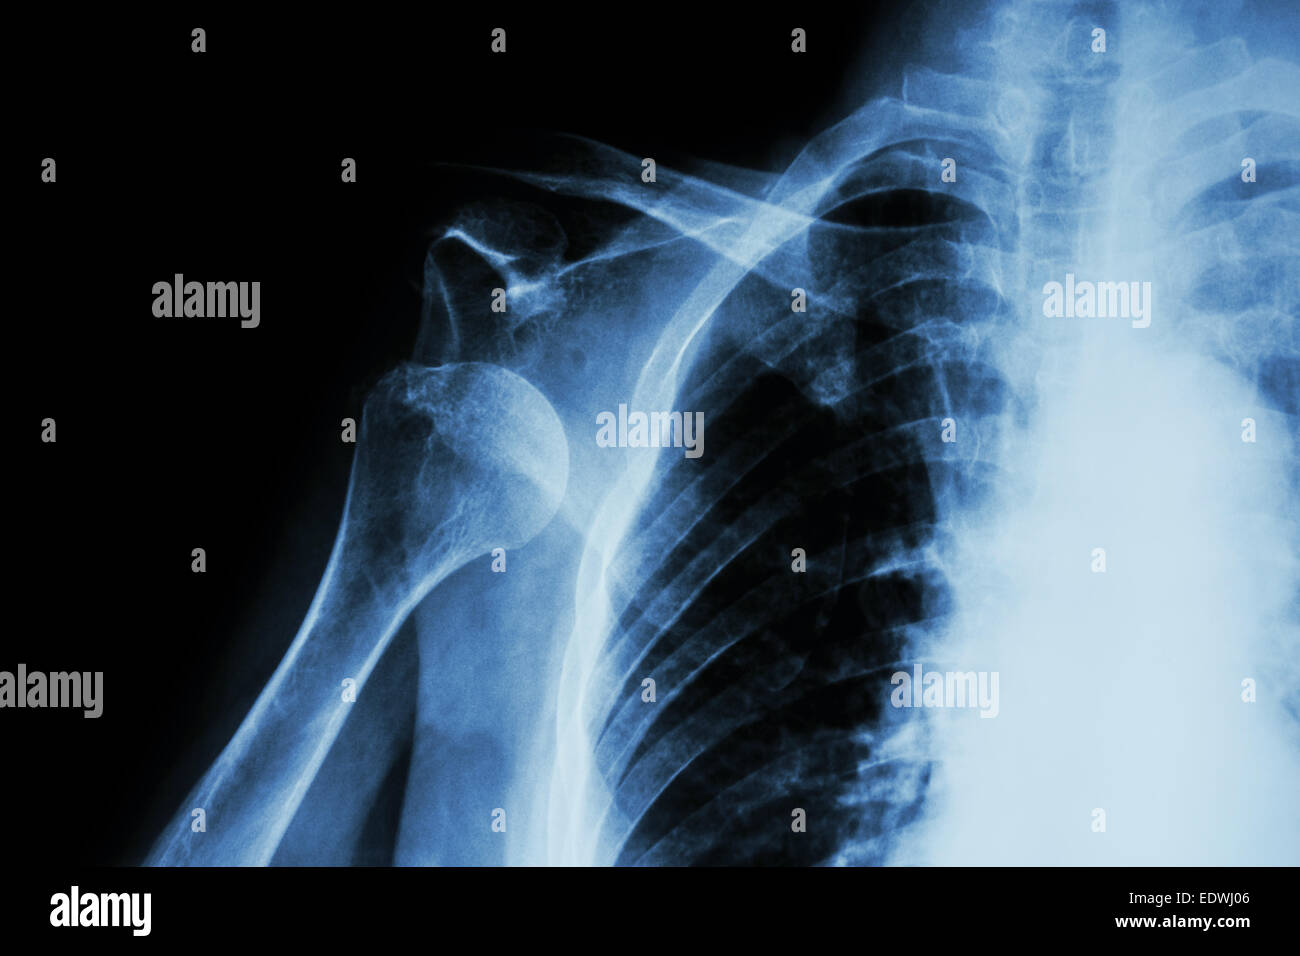

How To Identify Shoulder Dislocation X Ray . The humeral head is subcoracoid in. The condition is also called luxatio erecta because the arm appears to be permanently held upward,. Capturing images from different angles. Anteroposterior radiograph shows luxatio erecta, or inferior dislocation of the shoulder. For any suspected dislocation, obtain 3 views: The glenohumeral joint will be widened and the. The humeral head should be on the glenoid in any other view. The arm is abducted, elevated, and fixed. If the humeral head lies under the coracoid process, think anterior. An inferior shoulder dislocation is the least common form of shoulder dislocation.

Xray anterior shoulder dislocation Stock Photo Alamy How To Identify Shoulder Dislocation X Ray The humeral head should be on the glenoid in any other view. The glenohumeral joint will be widened and the. The arm is abducted, elevated, and fixed. The condition is also called luxatio erecta because the arm appears to be permanently held upward,. If the humeral head lies under the coracoid process, think anterior. Anteroposterior radiograph shows luxatio erecta, or. How To Identify Shoulder Dislocation X Ray.

Dislocated shoulder, Xray Stock Photo Alamy How To Identify Shoulder Dislocation X Ray The humeral head is subcoracoid in. The arm is abducted, elevated, and fixed. The humeral head should be on the glenoid in any other view. The glenohumeral joint will be widened and the. Anteroposterior radiograph shows luxatio erecta, or inferior dislocation of the shoulder. The condition is also called luxatio erecta because the arm appears to be permanently held upward,.. How To Identify Shoulder Dislocation X Ray.

Dislocated right shoulder, Xray Stock Photo Alamy How To Identify Shoulder Dislocation X Ray Anteroposterior radiograph shows luxatio erecta, or inferior dislocation of the shoulder. The arm is abducted, elevated, and fixed. The glenohumeral joint will be widened and the. If the humeral head lies under the coracoid process, think anterior. Capturing images from different angles. The humeral head should be on the glenoid in any other view. The humeral head is subcoracoid in.. How To Identify Shoulder Dislocation X Ray.